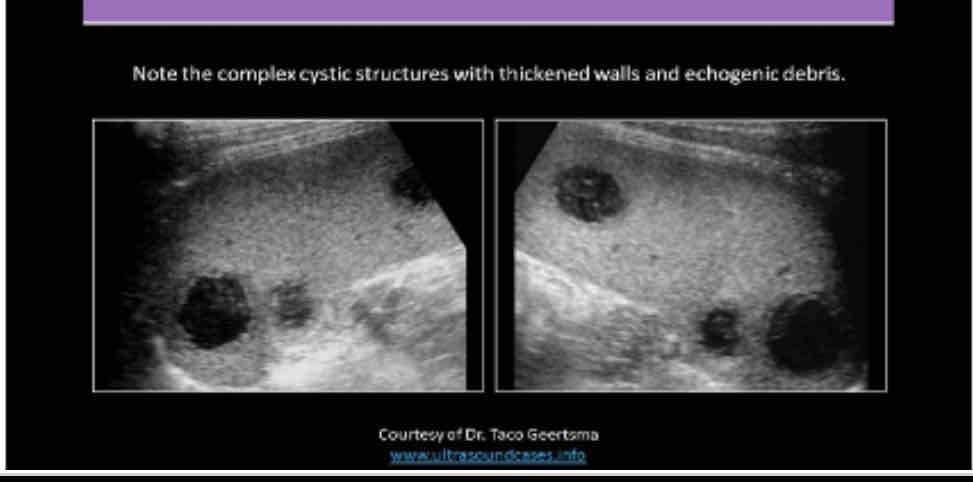

What does the following describe?

•It is rare. May be associated with endocarditis, septicemia and trauma

•May see them status post splenectomy

•Symptoms include pain, dizziness, faintness,

•Lab Testing: decreased hematocrit, fever, increased WBC and possible septicemia

splenic abscess

What does the following describe?

•Sonographically: Complex fluid collection with internal echoes

•Irregular borders

•May see septations and pleural effusion

•Dirty shadowing from gas producing organisms

splenic abscess